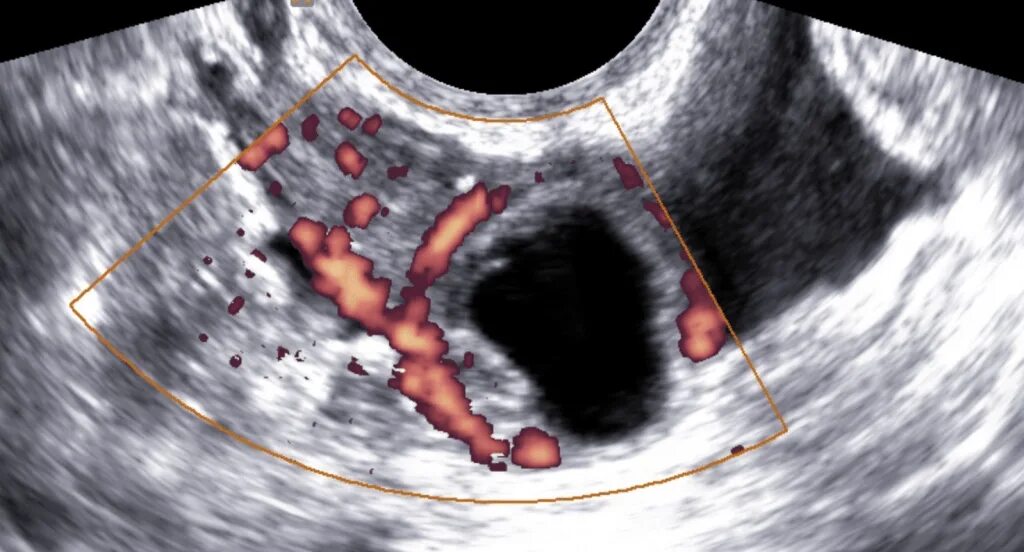

Эхо признаки кисты